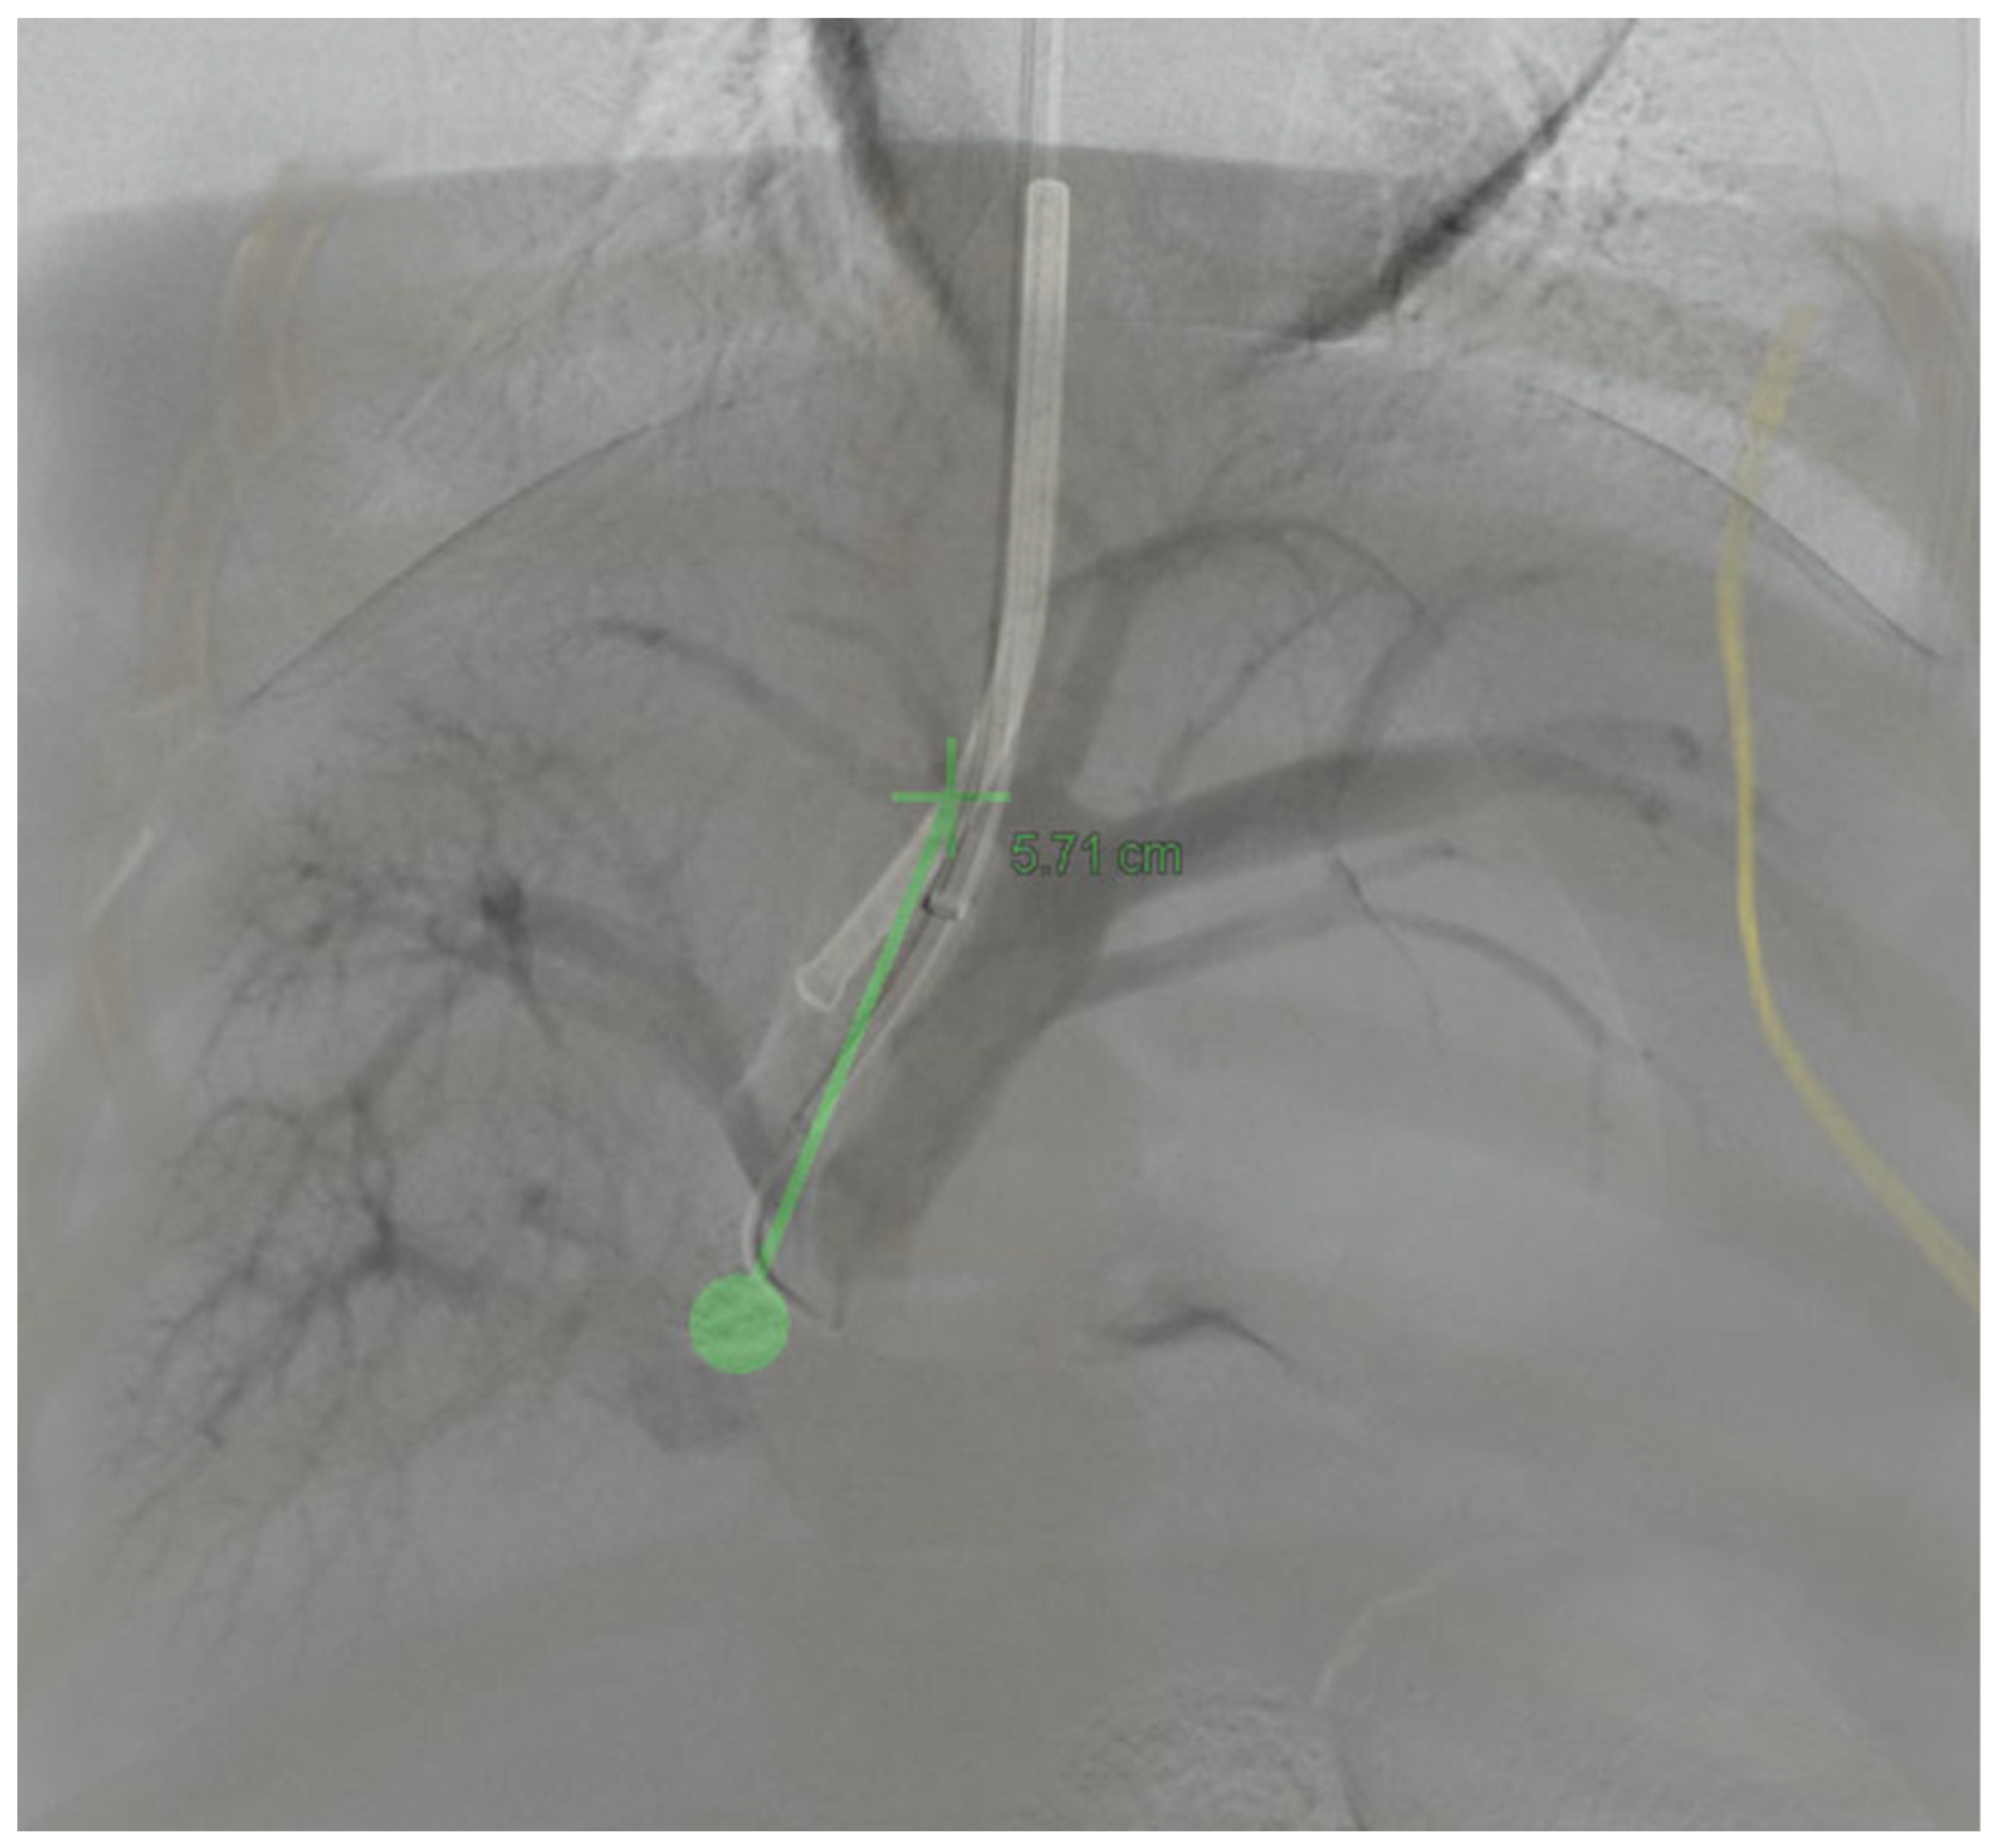

3.3. 3D Angiography-Guided TIPS Using CBCT/Angiography-Fused Images

3.4. 3D Angiography-Guided DIPS Using CT/CBCT/Angiography-Fused Images